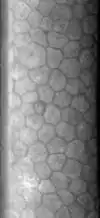

L’endothélium cornéen est une mono-couche cellulaire formant une mosaïque hexagonale. Ses cellules ne se régénèrent pas.